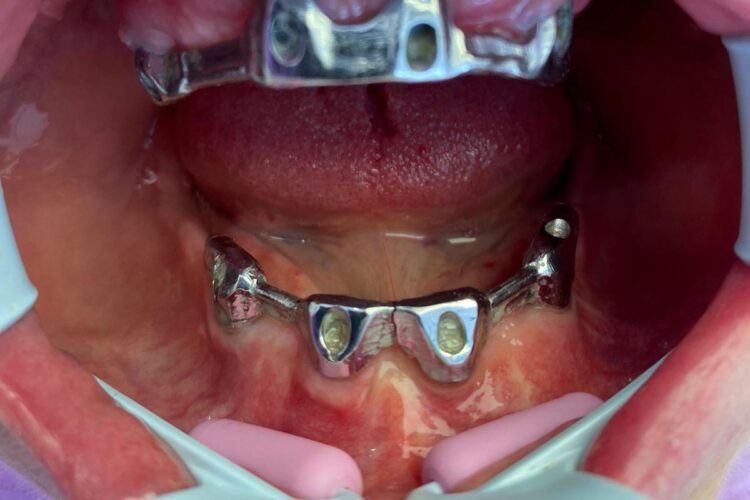

Pacienta in varsta de 75 ani, a pierdut dintii complet la ambele maxilare. Se prezinta in clinica si solicita proteze functionale fixe. Pentru refacerea arcadelor prin solutii implanto-protetice s-au inserat un numar mic de implante (4 implante superior si 4 inferior) care au fost folosite la constructia unei infrastructuri a protezelor, cu bara intre implante, capse laterale si suprastructura armata overdanture. Supraprotezele inserate pe bara satisfac estetica si functionalitatea ca o lucrare dentara fixa.